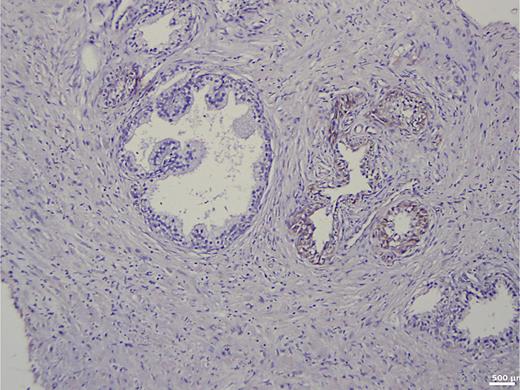

In the group of patients without carcinoma, the vast majority exhibited BSP expression of less than 1%. Twenty-nine out of thirty patients had a value below 5% (Table 1). One patient showed a BSP expression of 9%; however, the expression was observed only in basal cells in a condition of basal cell hyperplasia combined with chronic inflammation (Fig. 1). BSP expression in prostate tissue without carcinoma and without basal cell hyperplasia is shown in Figure 2.

Immunohistochemistry in prostate tissue without carcinoma and with basal cell hyperplasia.